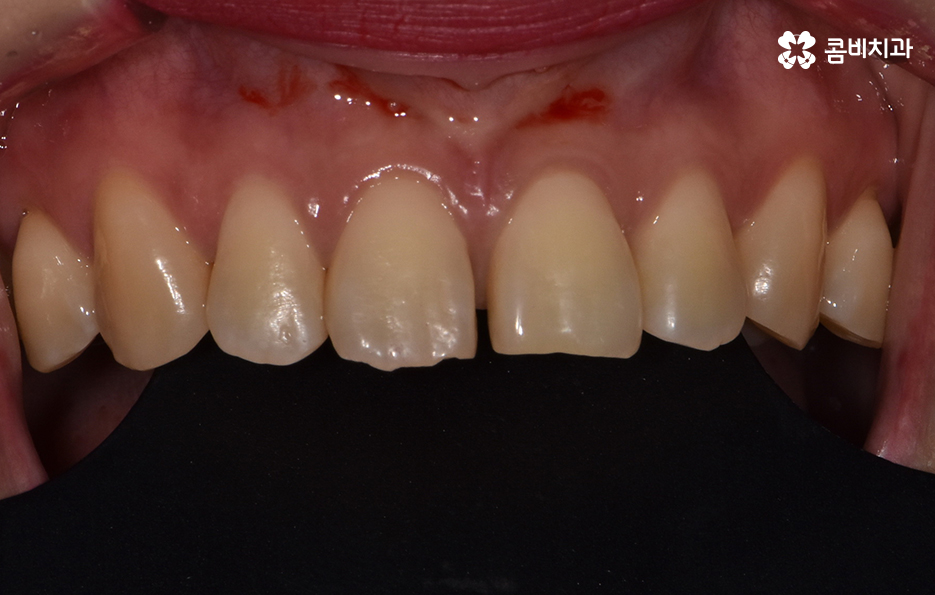

위 환자분의 경우 블랙트라이앵글 레진으로 치료를 하였는데

이러한 레진 치료의 장점은 빠르게 심미성을

회복할 수 있다는 점이며 비교적 저렴하다는 장점이 있습니다.

하지만 레진 치료는 영구적인 치료 방법이 아니며

추후 떨어질 수 있기 때문에 치료 후에도 꾸준한 관리는 물론

잇몸 치료를 꼭 함께 해주시는 것이 좋습니다.